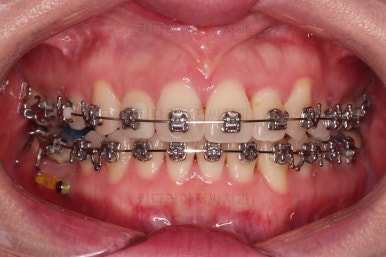

많이 삐뚤었던 앞니도 점점 좋아지는게 보이죠.

발치공간이 모두 닫히기 전에 얼굴모습에 대한 중간평가를 합니다.

입매가 너무 들어가거나 덜 들어가고 있진 않은지, 개선하고자 했던 중앙선은 마음에 드는지, 혹은 새롭게 고치고 싶은 무언가가 생겼다거나 등등

전반적으로 부산치과교정을 만족스럽게 진행 중입니다.